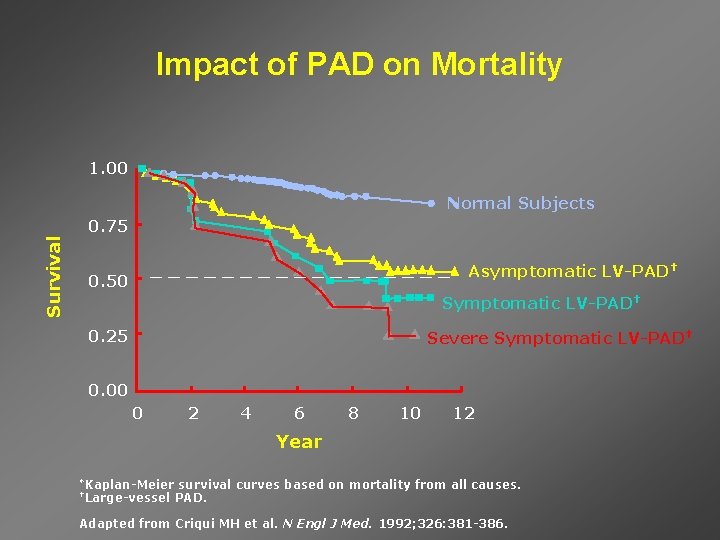

Impact of PAD on Mortality 1. 00 Normal Subjects Survival 0. 75 _________ 0. 50 Asymptomatic LV-PAD† Symptomatic LV-PAD† 0. 25 Severe Symptomatic LV-PAD† 0. 00 0 2 4 6 8 10 12 Year *Kaplan-Meier †Large-vessel survival curves based on mortality from all causes. PAD. Adapted from Criqui MH et al. N Engl J Med. 1992; 326: 381 -386.